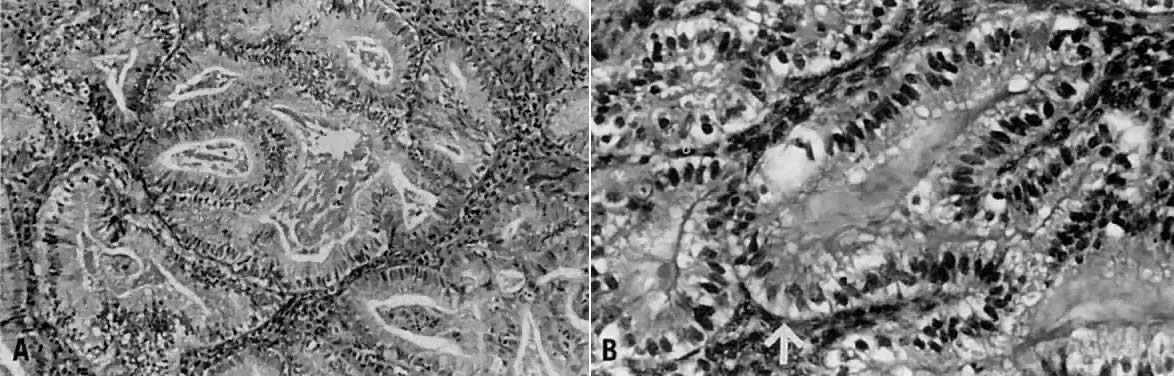

Villoglandular carcinoma is characterized by a papillary architecture with delicate fibrovascular stalks lined by cuboidal to columnar cells with minimal cellular stratification and mild nuclear pleomorphism (Fig. 5). Nucleoli are indistinct. It is important to distinguish this well-differentiated papillary variant of endometrial carcinoma from serous carcinoma, which is often papillary but displays grade 3 nuclear atypia with vesicular nuclei, prominent nucleoli, and necrosis.21,29 Serous carcinoma often forms papillary tufts, small clusters of cells that are detached from the papillary fronds. Psammoma bodies may be observed in either tumor type27 and are therefore not reliable distinguishing features. Villoglandular carcinoma only superficially invades the myometrium, being diagnosed at an early stage and thereby having a better prognosis than typical endometrioid carcinoma. To avoid confusion with papillary serous carcinoma, some authors refer to this entity as endometrioid adenocarcinoma with papillary architecture.

Fig. 5. ( A) Long papillary stalks lined by endometrioid-type cells are characteristic of the villoglandular or papillary variant of endometrial adenocarcinoma. ( B) The papillae are lined by stratified cells demonstrating mild nuclear atypia. Cellular budding and high-grade nuclear features are absent, aiding in distinguishing this lesion from serous carcinoma.